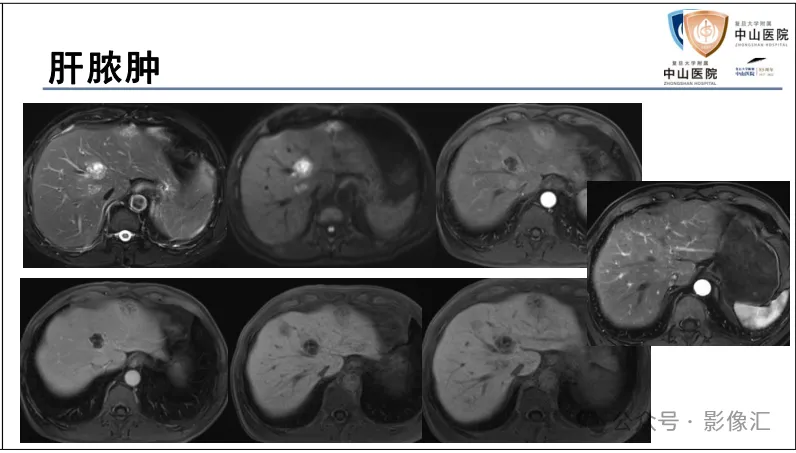

肝胆特异性对比剂增强肝胆图像判读方法与策略,课件来源于网络,作者复旦大学附属中山医院放射科饶圣祥教授。